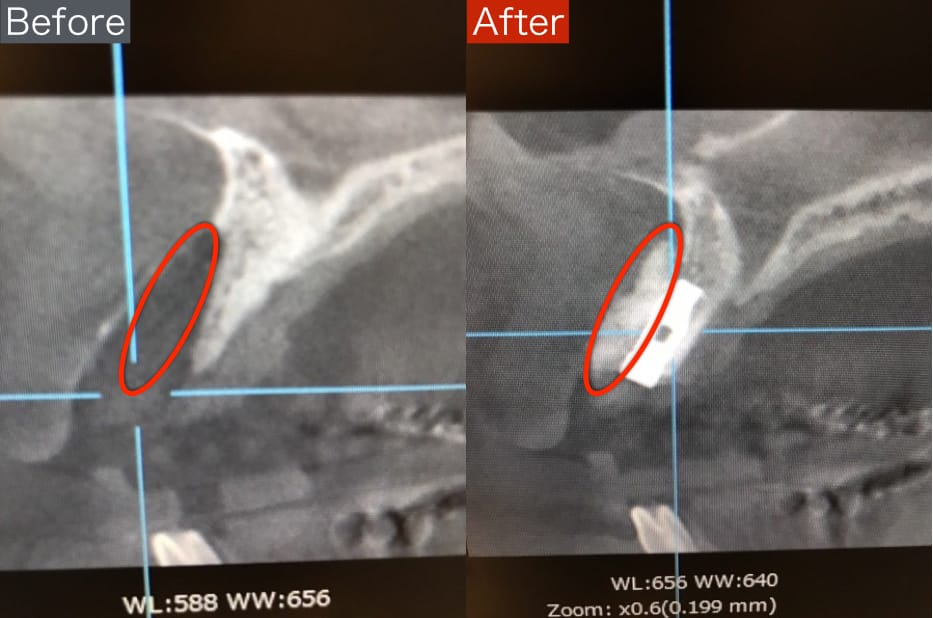

インプラント ソケットリフト法のBefore/After

【Before】

上顎洞(鼻の空洞)までの間隔が4mmしか無いため、しっかりとしたインプラント治療が行えない状態です。

【After】

お鼻の空洞を上げて骨を造成し、十分なスペースを確保することで、しっかりとしたインプラント治療が出来ています。

当院のソケットリフトは最小限の侵襲で骨を造成するので、お顔が腫れたり痛みが出ることがほとんどありません。

担当:理事長 佐藤悠野